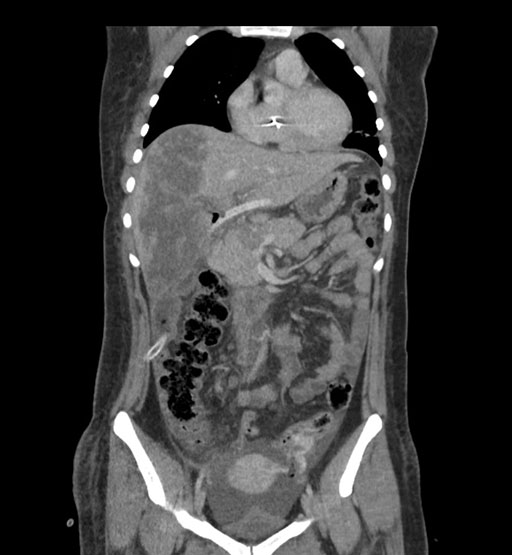

Coronal Arterial